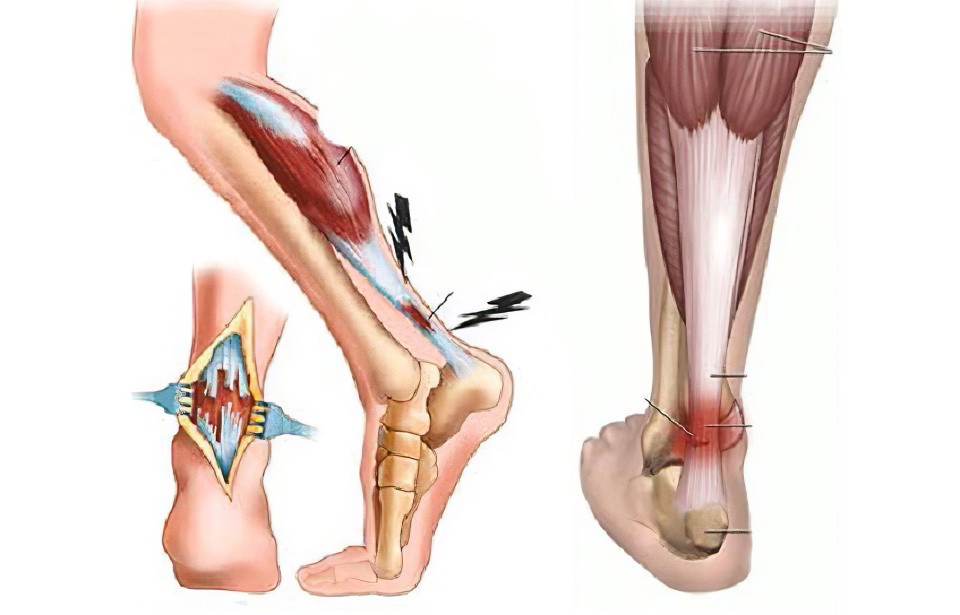

Тендинит ахиллова сухожилия

Это асептическое воспаление может затрагивать ткани, окружающие сухожилие (перитендинит), само ахиллово сухожилие (тендинит) или место его прикрепления к пяточной кости (энтезопатия). Все три формы могут проявляться отдельно или одновременно, а также перерастать в ахиллодинию и способствовать образованию пяточной шпоры. Тендинит возникает из-за постоянных нагрузок на голеностопный сустав или после единственного травматического воздействия на ахиллово сухожилие, например, у пожилых людей, которые внезапно начинают заниматься физической активностью.

Заболевание обычно развивается постепенно. Сначала пациент ощущает дискомфорт в области сухожилия, который отдает в пятку и беспокоит в основном по утрам. После разминки или короткой прогулки неприятные ощущения уменьшаются. Спустя несколько недель боль усиливается и становится постоянной, особенно при движении по лестнице или подъеме по наклонной поверхности. Икроножная мышца напряжена, лодыжка может покраснеть и немного отекать, а также ощущаться горячей на ощупь. Лечение тендинита ахиллова сухожилия обычно консервативное: требуется покой, тугое бинтование ноги, прием нестероидных противовоспалительных средств, физиотерапия и массаж. В случаях сильной боли могут проводиться инъекционные блокады с использованием стероидных гормонов.